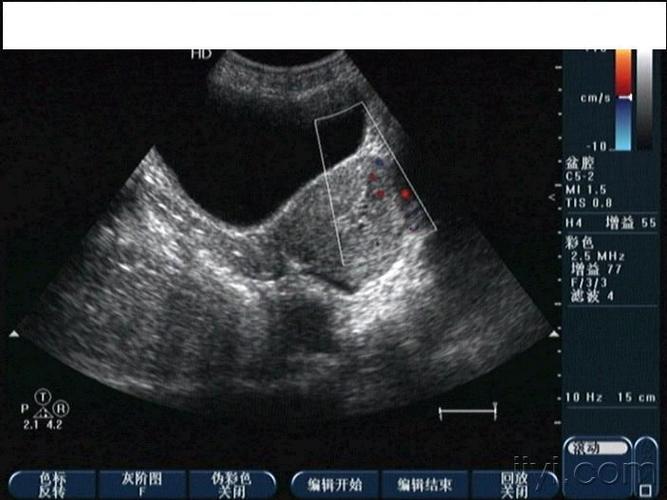

子宫穿孔彩超下表现

子宫穿孔彩超下表现,子宫穿孔超声表现图

典型人流术子宫穿孔

子宫穿孔的超声诊断

子宫穿孔超声表现图

子宫穿孔彩超图

子宫穿孔b超图片

子宫穿孔超声图片